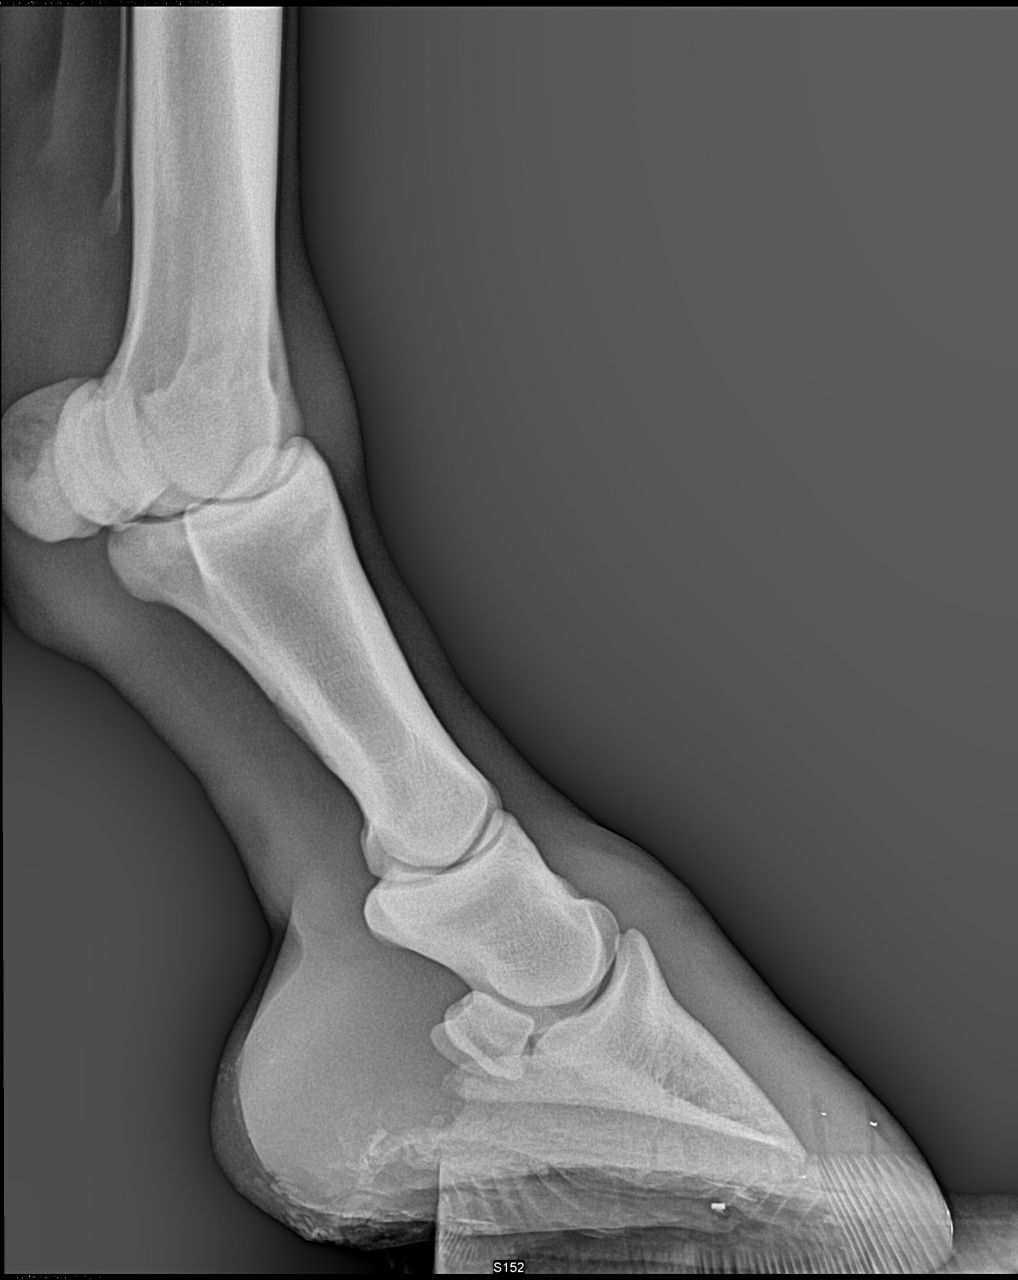

| Dire merci | Voici les premières radios de mon cheval de sa maladie antérieur droit ![]() ![]() |

| Dire merci | premieres radios antérieurs gauche![]() ![]() ![]() |

| Dire merci | les premières radios sont de juillet 2012 Voici les radios de l'antérieur droit fin septembre 2012 ![]() et celles de l'antérieur gauche ![]() ![]() |